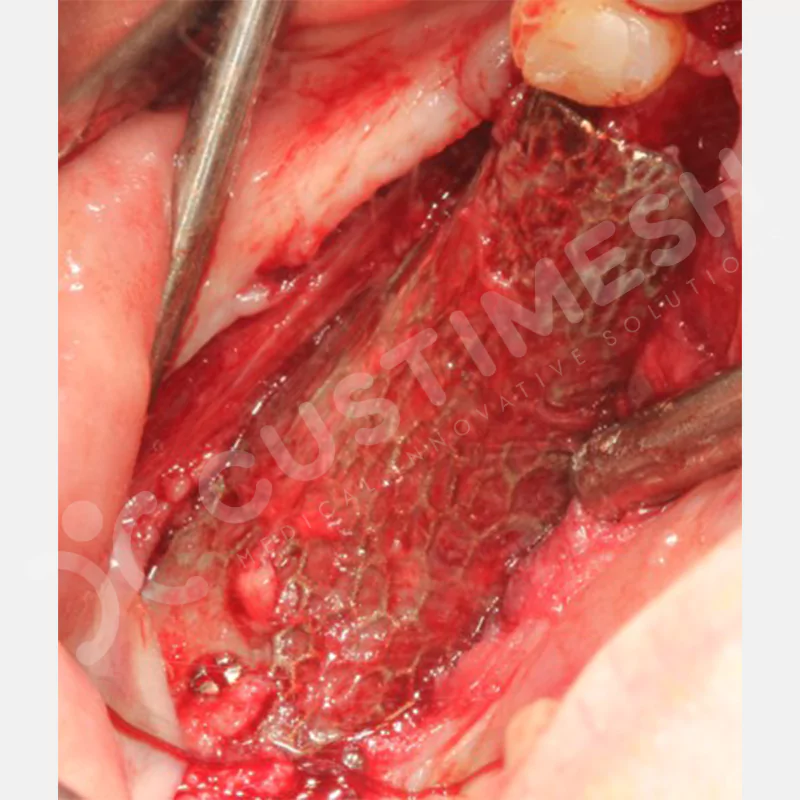

VAKA 1

VAKA 2

VAKA 3